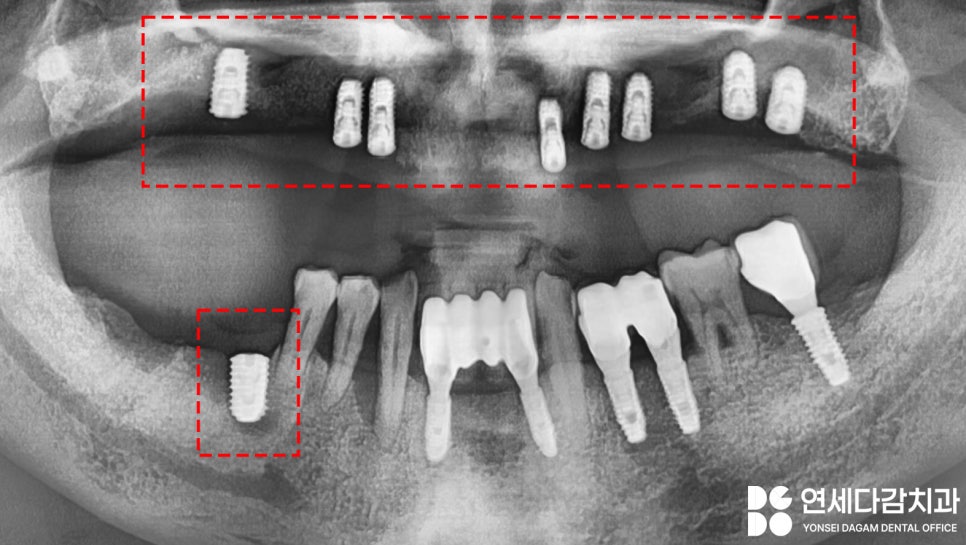

위에는 틀니를 사용하고 있었고

아래턱은 임플란트가 부분적으로

존재하고 있습니다.

이런 경우 적응을 못할 때가

많습니다.

왜냐하면 위에는

꼈다 뺐다 하는 가철성 장치이고,

아래는 뼈에 단단히 고정되어

있는 보철이므로

음식을 저작할 때 받는

힘이 다르기 때문이죠.

전체적인 진단 결과

가락시장역 치과 에서는

임플란트가 적합하다고 생각하였고,

골흡수로 인해 소실된 골의 높이를

뼈이식과 상악동 거상술을 동반한

수술을 통해 충분히 개선될 수

있다고 판단하였습니다.

양측 상악동에 측방 접근법을

통한 거상술을 시행한 뒤,

골이식재를 수복하였고,

총 8개의 픽스처를 식립했습니다.